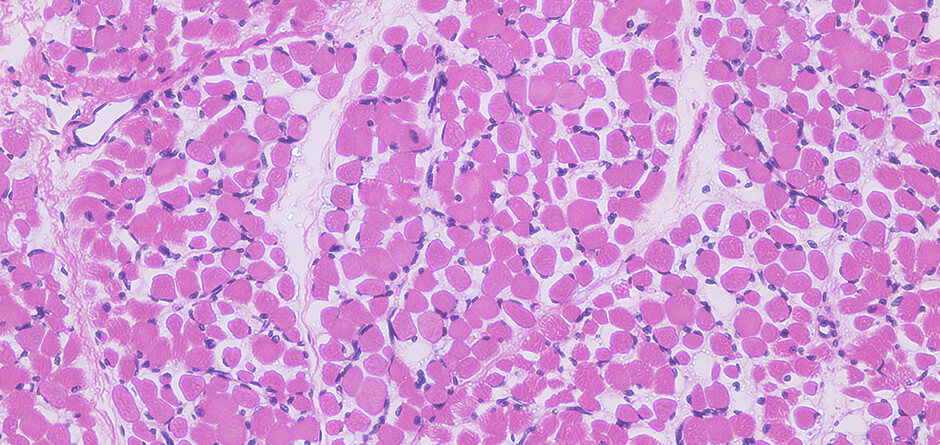

Animal tissues consist of cells at very high density and astounding level of organization. Conventional cell culture method involves stirring of cells inside a large tank. Cells may multiply, but tissues do not form. The method is far from the natural mechanism by which tissues efficiently and compactly form.

IntegriCulture collaborates with universities with state-of-the-art cell technology in fields of regenerative medicine, to develop unique methods of vascularization, tissue formation and cultivation, just as they happen in vivo.